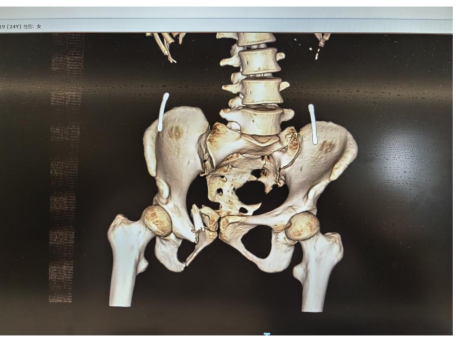

为了说清楚患者的伤情之严重性,继续上图一张,说明骶骨的位置。

患者的“骶骨骨折”,严重到什么程度?6月19日上午10点半,中心医院东院区的影像检查显示“第1-5骶椎骨折”。

*2025年6月19日患得影像学检查资料

刘华水主任解释说:“患者受伤后骨盆像风吹样,结构十分不稳定。腰下面的骨头叫骶骨,它是人体结构中重要的骨头,由五块骶椎融合而成,构成骨盆的重要部分。骶骨与骨盆起着传导重力和支持、保护盆腔脏器的作用,有很多的软组织附着。骶骨椎体骨折,必须第一时间手术干预,以避免进一步导致盆腔器官和神经功能损伤。”